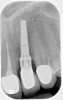

Fig 3. Fractured abutment screw.

Figure 3

Fig 4. Bending of the abutment prongs as a result of

motion caused by screw fracture.

Screw loosening and fracture (Figure 3 and Figure 4) have been consistent problems in implant dentistry.6 Several adaptations have been made to the screw and implant design to minimize these issues, such as the transition from an external to internal connection and changing both the screw composition and coating. Implant manufacturers offer various implant connection and screw designs, and these designs are modified as newer and enhanced materials become available.

Even with these advances, screw loosening and fracture are common. Five-year rates of screw loosening have been 0% to 5.8%.1 Factors that can contribute to this problem include a framework that does not passively fit, biomechanical overload, improper implant positioning, repeated tightening of the screws, inadequate tightening of the screws, settling of the screws, and improper screw design.7-9